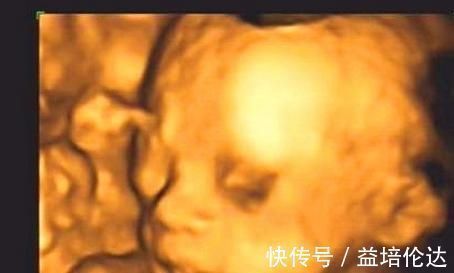

3.彩超中做鬼脸我们都知道,一般在准妈妈到了怀孕六个月左右的时候,就可以去医院里面做四维彩超这项检查了,通过四维彩超能够清楚的看到宝宝的模样以及宝宝的发育情况。如果准妈妈在做四维彩超的过程中,发现宝宝有稀奇古怪的表情时,这种现象是说明宝宝的大脑发育比较健全,点起来宝宝也是通过自己的这样的方式,间接的告诉着妈妈的心情如何,这种现象也是说明宝宝是个高智商的表现。